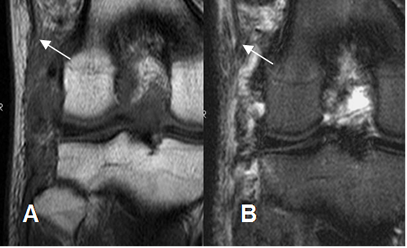

Fig 128. Lesión de la esquina posterolateral

A: RM coronal en STIR. Edema óseo del compartimiento medial, por trauma directo.

B: RM sagital y C: RM coronal en STIR. No visualización del ligamento arcuato, por ruptura.

D: RM coronal en STIR. Cambios inflamatorios que rodean el LCL, el cual muestra ruptura de algunas fibras, por esguince G II.